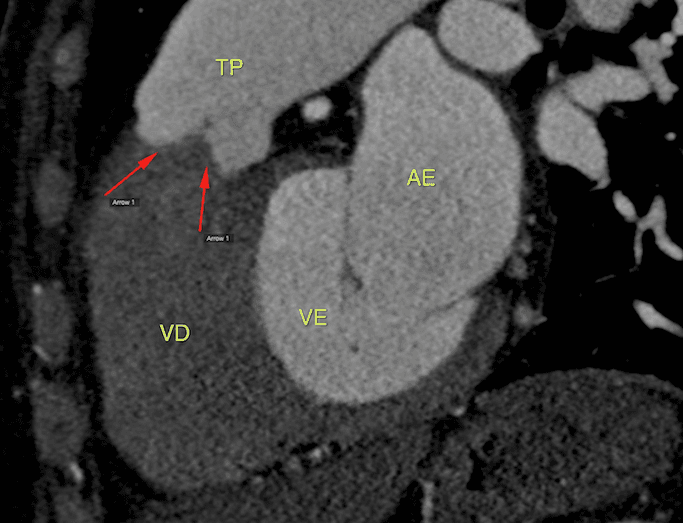

Mulher de 61 anos veio para avaliação cardiológica devido à dor torácica e dispneia aos esforços. Negava tabagismo ou doença pulmonar prévia. Achado no exame físico de sopro sistólico rude em borda es…